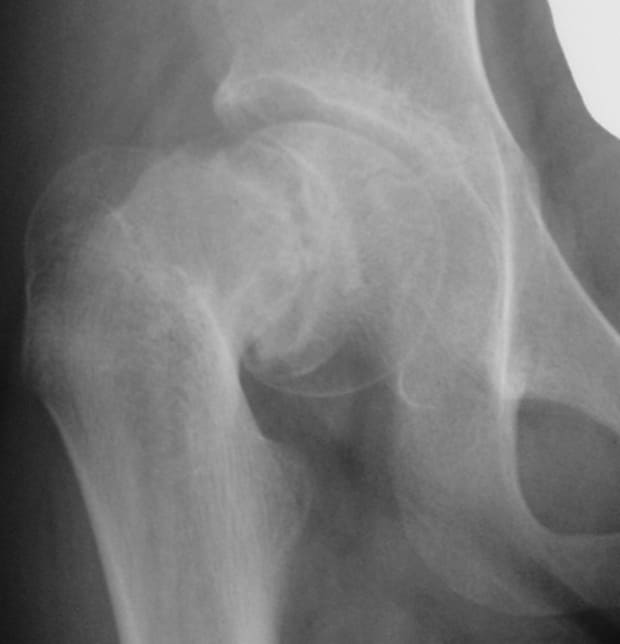

1. 思春期の「体格が良い子」は要注意!大腿骨頭すべり症

10歳〜15歳くらいの、少しふっくらとした体型の男の子に多く見られるのが「大腿骨頭すべり症(だいたいこっとうすべりしょう)」です。

- どんな病気?: 股関節の「頭(大腿骨頭)」が、成長板(骨が伸びる場所)からズレてしまう病気です。

- 見逃せないサイン: 「急に強い痛みが出て歩けなくなる(急性)」場合もあれば、「なんとなく足を引きずる、膝が痛い(慢性)」場合もあります。

「膝が痛い」と言っているのに膝の検査で異常がない場合、専門医は真っ先にこの病気を疑います。これは時間との勝負になることもあり、緊急で手術が必要になるケースも珍しくありません。